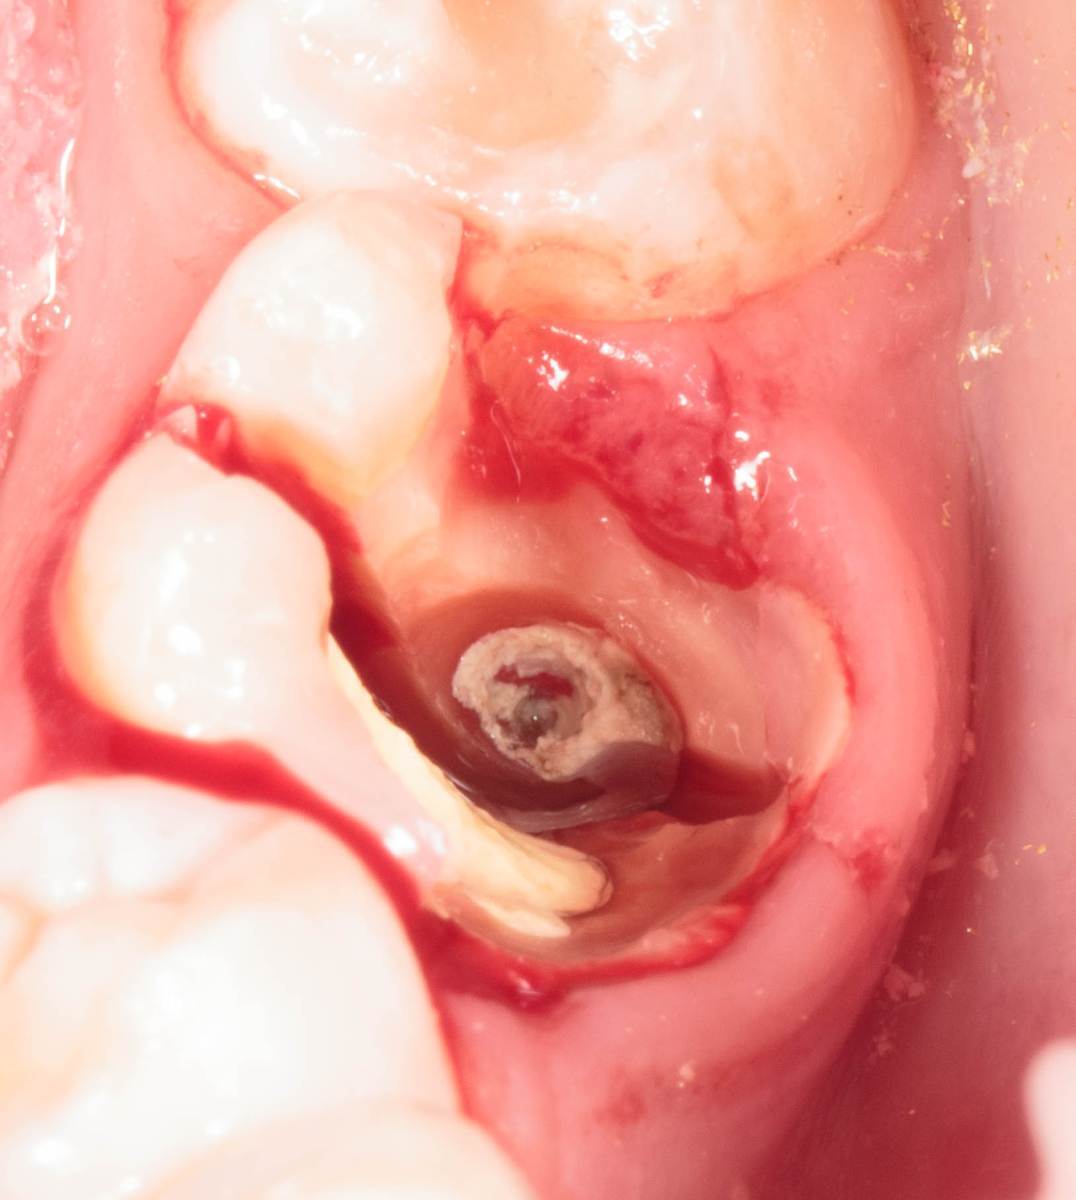

Женька Опубликовано 28 ноября, 2025 Поделиться Опубликовано 28 ноября, 2025 Всем привет, коллеги! 14 лет, терапевты ставят трещину по КТ (снимков до, к сожалению нет, косяк, каюсь). чуть сепарировав зуб и глянув на зуб под отлетевшим куском пломбы трещина "подтвердилась". Кейс на фото. Из интересного - маленький реколл в 1.5 года и спокойное перемещение зуба брекетами! 4 1 2 Ссылка на комментарий

Женька Опубликовано 17 декабря, 2025 Автор Поделиться Опубликовано 17 декабря, 2025 @сирена вот и завтра наступило) прощу прощения, что так долго, всё из головы вылетало на работе посмотреть. Пересадили в конце мая, к ортодонтии подключили в начале сентября ~3.5 месяца прошло с пересадки на тот момент. 1 Ссылка на комментарий